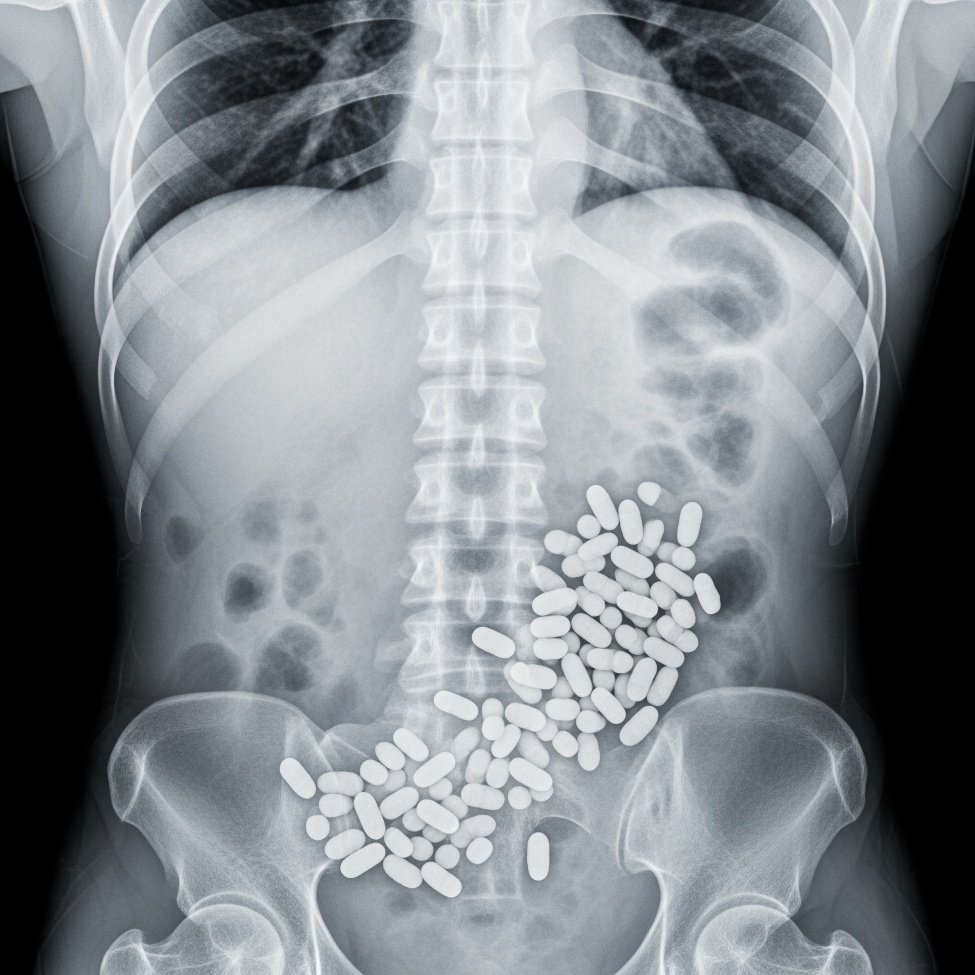

C'est un drame qui a d'abord intrigué les enquêteurs. Le 26 janvier 2025, à bord d'un vol reliant Paris à La Réunion, un passager âgé de 40 ans, originaire de Montpellier (Hérault), décède subitement. À l'époque, les circonstances de sa mort restent floues. Mais l'autopsie, révélée par Midi Libre ce jeudi 16 avril, a levé le voile sur une vérité glaçante. Le père de famille transportait dans son corps 77 ovules de cocaïne. L'un des préservatifs qui emballaient la drogue a cédé en plein vol, provoquant une overdose massive qui lui a été fatale. À 10 000 mètres d'altitude, aucune réanimation n'a pu le sauver.

Cette affaire rappelle les risques extrêmes pris par ces transporteurs de drogue que l'on appelle les “mules” ou “passeurs digestifs”. Avaler des dizaines d'ovules de cocaïne, parfois plus d'une centaine, expose à un danger mortel. La moindre fuite, le moindre préservatif défectueux, peut provoquer une overdose foudroyante. Dans ce cas précis, les 77 ovules découverts dans le corps du quadragénaire représentent une quantité considérable. Leur valeur sur le marché noir se chiffre en milliers, voire en dizaines de milliers d'euros. Mais pour la victime, c'est un prix bien trop lourd à payer.